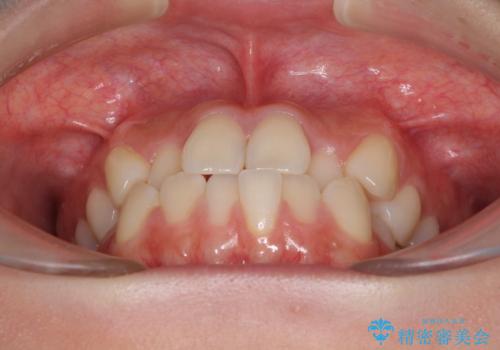

舌側転位している側切歯特有の、切縁の位置が不揃いであったり、根元が内側に引っ込んだ状態であったりという、インビザライン独特の仕上がりになることなく、きれいに整った歯列とすることができました。

- 前歯のクロスバイトが気になり、インビザラインによる矯正治療を希望して来院された患者様です。

上顎側切歯(上の真ん中から2番目の歯)が舌側転位している場合、インビザラインでは仕上げきれないことが多く、更には無理して動かそうとすると歯髄壊死を起こすリスクが高いと言われています。

インビザラインで歯列を移動する前に、上顎前歯をワイヤー矯正で整え、その後上下歯列をインビザラインにて矯正治療を行うこととしました。